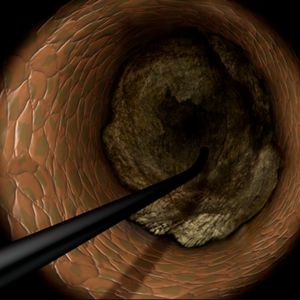

A new wave of technological innovation emerged in the late 2010s with the introduction of the 3D wiring technique. Developed by Dr. Atsunori Okamura of Sakurabashi Watanabe Hospital, this method enabled three-dimensional visualization of wires within occluded lesions, allowing precise manipulation by observing the movement of the wire tip in three dimensions. This rational approach transitioned CTO-PCI wiring from a skill dependent on tactile sensation to one guided by scientific observation.

The 3D wiring technique was further refined by expert operators across Japan, eventually establishing Tip Detection Antegrade Dissection Re-entry (TD-ADR) as a new standard in CTO-PCI. TD-ADR reignited global interest in CTO-PCI by providing a more systematic and reproducible methodology. More recently, HydroDynamic Contrast Recanalization (HDR) has emerged as a technique for performing antegrade CTO-PCI, leveraging the synergistic use of contrast microinjections and polymer-jacketed wires to further expand the technical options available for CTO-PCI.